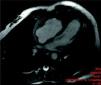

Ten days after discharge, the patient experienced recurrence of chest pain, with no fever. Control TTE showed RV apical hypokinesia and an apical mass of the same signal intensity as the myocardium with no cleavage plane between the mass and the myocardial wall (Figure 2). Pericardial thickening persisted with a moderate effusion. In the light of the new findings, the RV mass was considered to be a thrombus or tumor, or to be secondary to hypereosinophilic syndrome. Oral anticoagulation with warfarin was begun given the suspicion of a thrombus and the patient was transferred to Coimbra University Hospital for cardiac magnetic resonance imaging (CMRI) and endomyocardial biopsy (EMB). CMRI revealed marked thickening of the RV apex, of infiltrative appearance (Figure 3). Delayed enhancement showed heterogeneous areas of hyperintense signal in the RV apex, septal wall and LV apex, some of which had a subepicardial distribution. EMB revealed fragmentation of muscle bundles by eosinophils, with myocyte destruction and coagulation necrosis, compatible with eosinophilic endocarditis. The diagnosis of Loeffler's endocarditis was therefore established and treatment begun with oral prednisolone (1mg/kg/day), anticoagulation with warfarin being continued. During follow-up, the patient was completely free of pain, her eosinophil count normalized and the RV myocardial thickening disappeared (Figure 4), confirmed by CMRI (Figure 5). Anticoagulation was maintained for three months and corticosteroid therapy for six months. She subsequently had one episode of sustained back pain without hypereosinophilia or echocardiographic alterations, and was treated with corticosteroids for four weeks. The patient has been evaluated every six months by ECG, laboratory tests and TTE, and three years after beginning treatment, control CMRI shows her to be in complete remission.